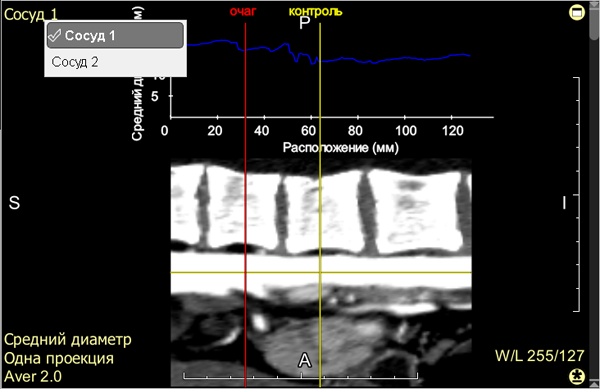

5 - Vessel longitudinal view and the vessel lumen graph above it

Place the red linear cursor ("Lesion") on the longitudinal view, referencing the graph above it, in the area of minimal vessel lumen:

Move the yellow linear cursor ("Control") on the longitudinal view to an obviously "normal" vessel lumen area:

If more than one vessel has been constructed, you can select another vessel for stenosis analysis without switching to the Vessel Construction mode

Click in the active overlay of the longitudinal view on another vessel from the list: